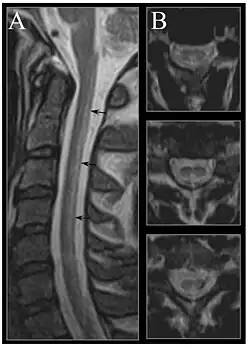

Image of the cervical spinal cord in vitamin B12 deficiency showing subacute combined degeneration. (A) The midsagittal T2-weighted image shows linear hyperintensity in the posterior portion of the cervical tract of the spinal cord (black arrows). (B) Axial T2-weighted images reveal the selective involvement of the posterior columns. | |

Severe vitamin B12 deficiency is associated with subacute combined degeneration of the spinal cord, which involves demyelination of the posterior and lateral columns of the spinal cord.[101] Symptoms include memory and cognitive impairment, sensory loss, motor disturbances, personality changes, disorientation, irritability, dementia, loss of posterior column functions and disturbances in proprioception.[102][103][104] In advanced stages of vitamin B12 deficiency, cases of psychosis, paranoia and severe depression have been observed, which may lead to permanent disability if left untreated.[101][102][103] Studies have shown the rapid reversal of the neurological symptoms of vitamin B12 deficiency, after treatment with high-dose of vitamin B12 supplementation; suggesting the importance of prompt treatment in reversing neurological manifestations.[105]

MRI of the brain may show periventricular white matter abnormalities. MRI of the spinal cord may show linear hyperintensity in the posterior portion of the cervical tract of the spinal cord, with selective involvement of the posterior columns.